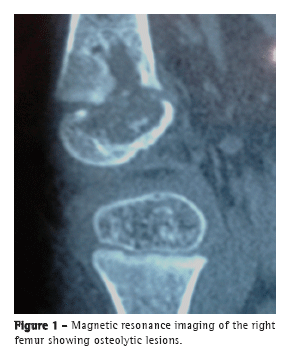

A female infant (age, 2 years and 4 months) from the city of São Paulo, Brazil, had been vaccinated with BCG in the maternity ward and presented with a 15-day history of pain in the right leg and impaired ambulation. The patient was treated with a nonsteroidal anti-inflammatory drug and showed improvement. However, two weeks after the drug had been discontinued, she showed worsening. An X-ray of the knee showed an osteolytic lesion in the right distal femoral epiphysis. Magnetic resonance imaging (Figure 1) revealed a centromedial lesion in the right distal femoral epiphysis, with multiple areas of cortical erosion; there was significant cortical discontinuity, and there was no effusion in the posteroinferior portion of the medial femoral condyle. The patient was treated with ceftriaxone for 14 days, with no improvement. A punch biopsy of the right knee showed a granuloma with no AFB. The patient was started on isoniazid, rifampin, and pyrazinamide. Investigation of her parents, siblings, and nannies showed no exposure to pulmonary or extrapulmonary tuberculosis. At admission to our facility, a few days after treatment initiation, the patient was in good general health. The only abnormality on physical examination was right knee edema (distal and proximal to the tibia). The edema was cold and painful on palpation, being accompanied by functional disability.